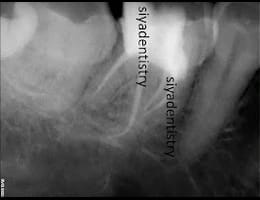

The dentist examines the tooth and takes X-rays to confirm the extent of infection or damage.

DIGITAL X RAY “RVG”

We invest in the latest imaging technologies like Carestream RVG IOPA to provide superior diagnostic capabilities.

Expert Analysis:

Our experienced dental team is skilled in interpreting RVG IOPA images, ensuring that any dental issues are accurately identified and addressed.